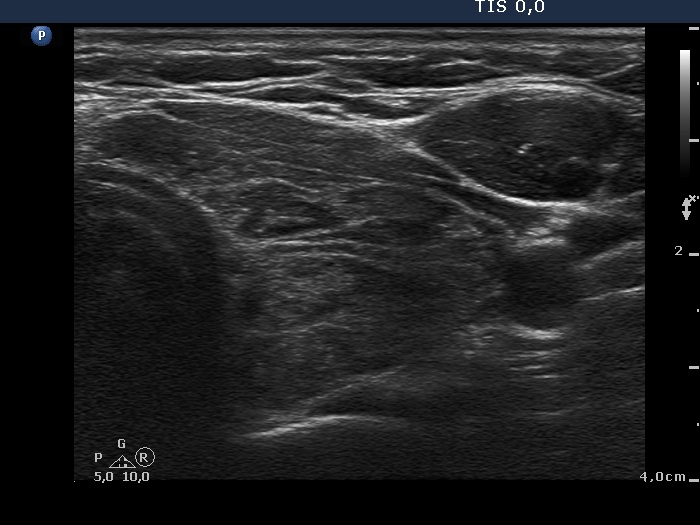

The micronodular pattern is usually stable. The thyroid is more often enlarged than in other forms of hypothyroidism.

- As in most cases of micronodular presentation, the presence of true nodule or nodules cannot be ruled out or justified.